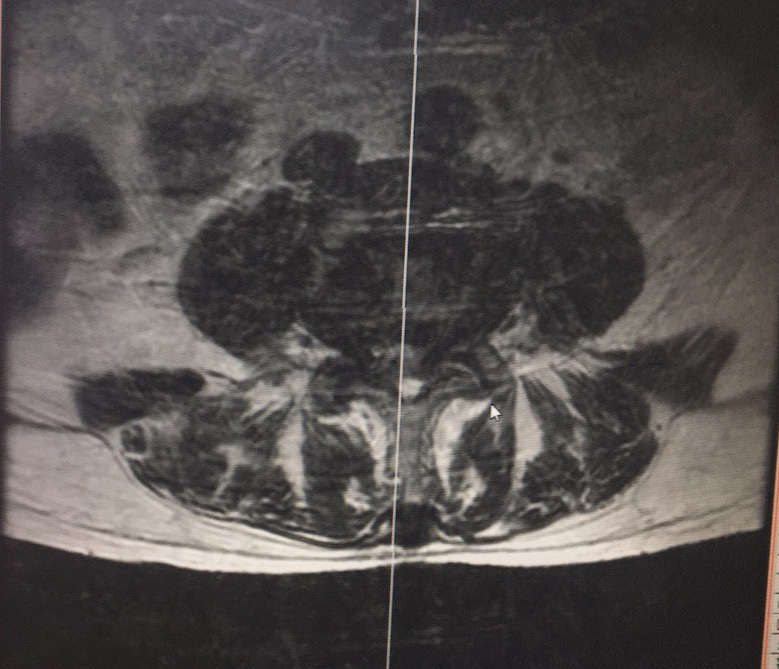

視野清晰,

(圖示:神經根暴露充分,減壓徹底,確保療效)

總結:UBE技術微創,療效好,對椎管狹窄等疾病具有良好的療效